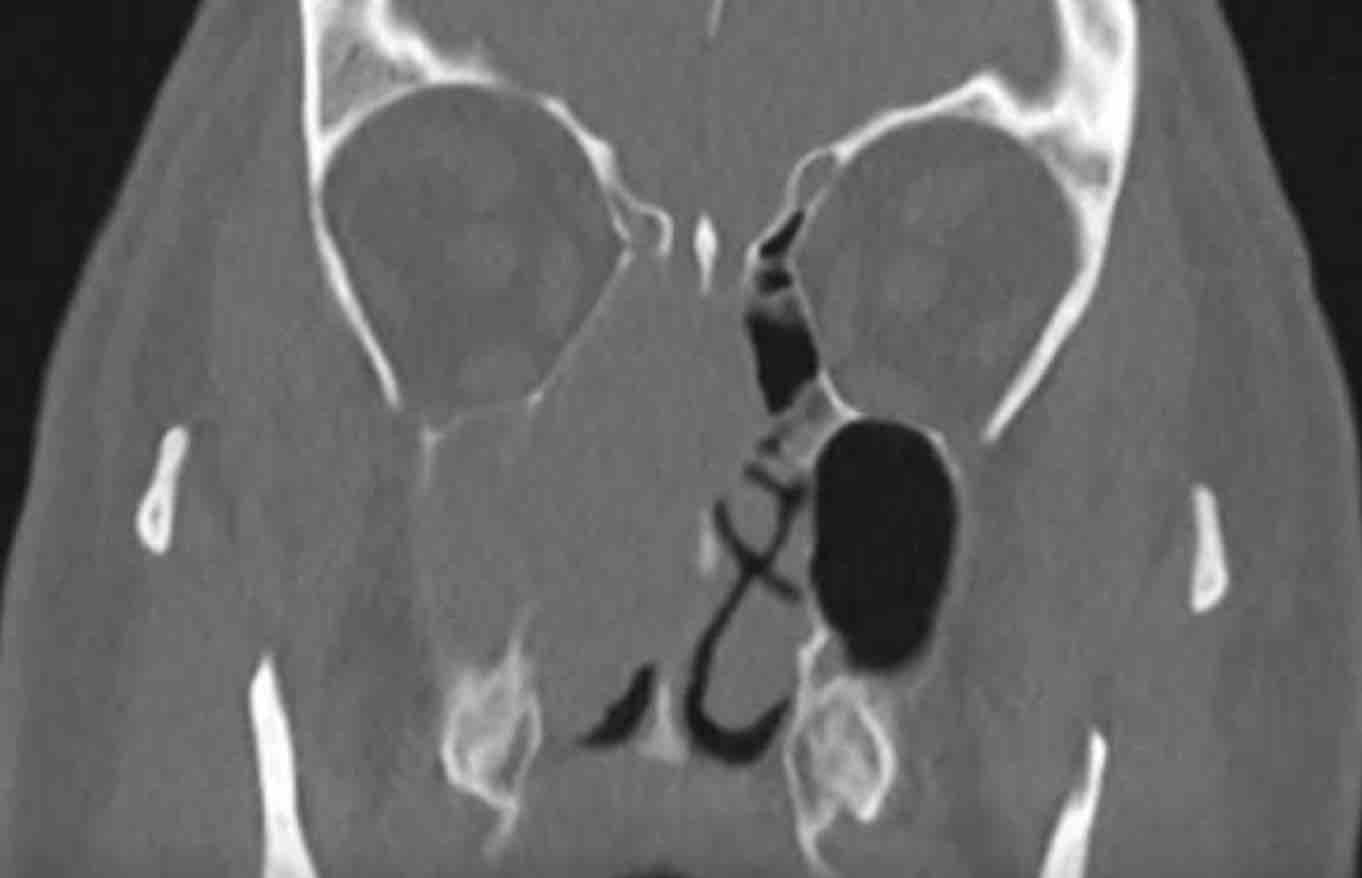

Bệnh nhân nữ 62 tuổi.

CT xoang được chỉ định bởi bác sĩ tai mũi họng. Thông tin lâm sàng: ‘viêm xoang một bên mạn tính’.

Hình ảnh

Có hình ảnh mờ đặc do mô mềm tại xoang hàm, xoang sàng và xoang trán bên phải (gọi là ‘kiểu tắc nghẽn phễu’).

Như đã đề cập, đây là một dấu hiệu cảnh báo.

Hãy quan sát các hình ảnh tiếp theo và cố gắng xác định liệu có tổn thương ác tính nào gây ra kiểu tắc nghẽn phễu này không (hay có nguyên nhân nào khác không?)

Có hình ảnh thấu quang quanh chóp răng tại vùng chân răng hàm lớn trên bên phải, gợi ý nhiễm trùng răng (đầu mũi tên đen).

So sánh với bên trái bình thường trên ảnh cắt ngang (đầu mũi tên trắng).

Thăm khám lâm sàng bổ sung đã loại trừ tổn thương ác tính.

Bệnh nhân được chuyển khám răng hàm mặt vì nhiễm trùng răng hoàn toàn có thể là nguyên nhân gây viêm xoang mạn tính một bên.

Lưu ý: Vì lý do này, việc bao gồm vùng xương hàm trên trong trường chụp của CT xoang là điều hết sức quan trọng.